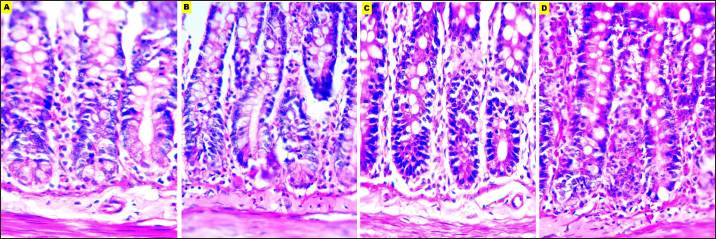

The microscopic evaluation of the liver, kidney, brain, and small intestine sections was analyzed to assess the adequacy of fixatives, the parameters of staining affinity, cellular outline, cytoplasmic attributes, nuclear attributes, and overall structural evaluation were targeted.

EZAT solution showed a significantly higher staining affinity with hematoxylin and eosin particularly in the kidney and brain slides. The grade was (very good) compared with (fair) to (good) grades in the formalin-based solutions. There were no significant differences noticed in the slides of the liver and small intestine, and staining grades were closely equivalent.

EZAT solution also was the best for cellular outline demonstration, cellular architecture and tissue details were clearer in the liver, kidney, brain (cerebral cortex), and small intestine sections compared with formalin-based slides. Grades ranged from very good (4 ± 0.21) in kidney to good (3.71 ± 0.47), (3.71 ± 0.47), and (3.43 ± 0.57) in liver, brain, and small intestine with EZAT slides, and was the worst with formalin 10% which ranged from fair (2.57 ± 0.36), (2.28 ± 0.52), and (2.28 ± 0.35) in liver, brain, and small intestine to poor (1.71 ± 0.28) in kidney.

According to evaluators, the cytoplasmic attributes were also enhanced in the EZAT solution, and the grade ranged from very good (4.14 ± 0.69), (4.14 ± 0.26) in kidney and brain sections to good (3.71 ± 0.47), (3.57 ± 0.36) in liver, and small intestine slides. Statistical differences were noted between EZAT and formalin-based fixatives in kidney and brain slides, while there were no differences observed in liver and small intestine slides. Furthermore, the nuclear attributes were superior with EZAT solution compared with formalin-based fixatives, and grades were significantly different in the kidney, brain, and small intestine, varying from very good (4 ± 0.43) in the kidney to good (3.85 ± 0.50), (3.42 ± 0.57), and (3.28 ± 0.42) in the brain, small intestine, and liver.

The overall structural evaluation revealed excellent microscopic appearance with EZAT slides across all types of tissues, characterized by less tissue disintegration, fine cellular details, sufficient nuclear staining, and improved morphological presentation, grades for this parameter were between 4.28 and 4.14 in the kidney and brain slides, which is significantly better than formalin 10 % and NBF (Figs. 47; Table 1). These results suggest that EZAT provides better tissue preservation and staining quality compared with traditional common fixatives.

Fig. 6. Microphotographs of Hematoxylin and eosin-stained brain sections preserved in different fixatives included, formalin 10% (A), NBF (B), formalin 4% (C), and EZAT solution (D) at 400x magnification.

Fig. 7. Microphotographs of Hematoxylin and eosin-stained small intestine sections preserved in different fixatives included, formalin 10% (A), NBF (B), formalin 4% (C), and EZAT solution (D) at 400x magnification.

EZAT fixative enhanced morphological and histological details compared with formalin-based fixatives in this study, these findings are consistent with the findings of Wester et al. (2003), which attributed that improvement to the efficient preservation of the cellular protein and nucleic acid. Beckstead (1994) also recommended using zinc-containing fixatives to provide superior morphological preservation for routine and immuno-stained tissue sections.

The chemical composition of the EZAT solution enhanced cytoplasmic and nuclear properties, which properties included: nuclear membrane integrity, nuclear homogeneity, and better DNA, and RNA presentation. While cytoplasmic properties included: structural integrity, permeability, enzymatic activity, and ionic balance (Howat and Wilson, 2014; Steicke et al., 2018).

The overall structural evaluation revealed excellent microscopic appearance with EZAT slides, these observations corresponded with Wester et al. (2003), Bonds et al, (2005), Lykidis et al. (2007), Jensen et al. (2010), and Mori et al. (2015) findings in different zinc-containing formulas compared with NBF, formalin 4% and 10 % fixatives.